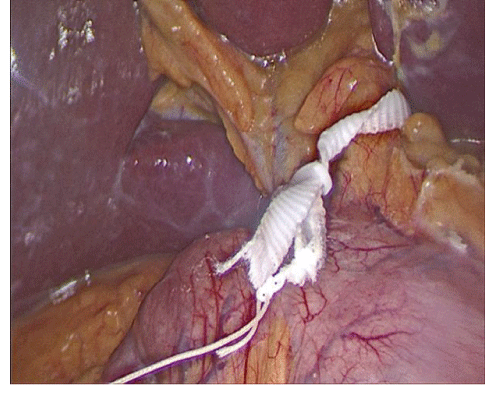

Laparoscopic Treatment of Larrey Morgagni Hernia with an Assorbable Suture

Pozzo G*, Castellano E, and Sciacca C

Morgagni-Larrey hernia is a very rare congenital diaphragmatic hernia, with an incidence of 2-5% of all diaphragmatic hernias and is usually diagnosed incidentally in asymptomatic adults. In this case report, we present a 55-year-old man with intestinal obstruction-like symptoms...